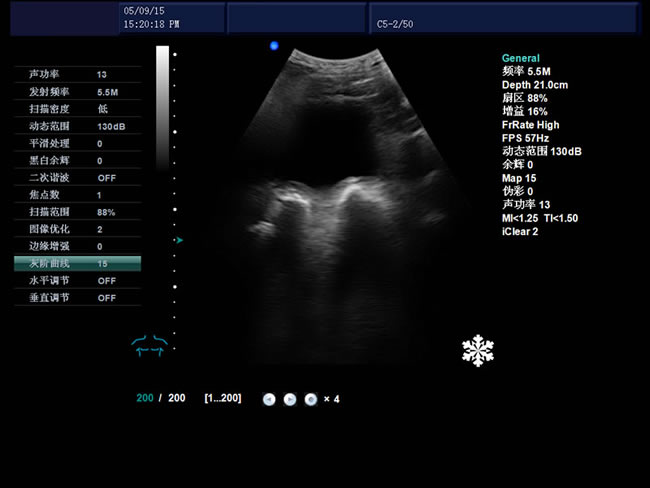

S9 彩色多普勒獸用超聲診斷儀

• S9彩色多普勒獸用超聲診斷儀是徐州市大為電子設備有限公司推出的一款全新的彩色超聲診斷儀器。

• 臨床應用